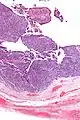

Micrograph of transitional cell carcinoma of the ovary. H&E stain.

TCC of the ovary is diagnosed by examination of the tissue by a pathologist. It has a characteristic appearance under the microscope and distinctive pattern of immunostaining.[2]